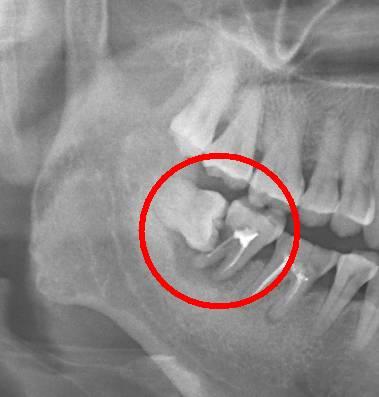

2、是否經常發炎:經常發生急性智齒冠周炎是難受的,有劇烈的疼痛,臉部腫脹等,而且對於(yu) 咀嚼食物,張嘴說話等都會(hui) 有一些影響,如果經常發炎,且位置不正,建議消炎後及時去除。

3、阻生智齒定在鄰牙上,暫時沒有症狀,需要先觀察情況。為(wei) 了更好的保護鄰牙,建議拔除智齒。

智齒一般在口腔內(nei) 的數量的,每個(ge) 人都是不同的,有的沒有,有的有4顆,而且智齒拔牙雖然是比較普遍的,但是對於(yu) 醫生的技術是比較高的,所以建議大家都能考慮清楚,到底要不要拔牙,如果智齒萌出位置正,有對咬牙,沒有炎症的情況可以暫時觀察。一旦出現問題,則需要及時拔除。